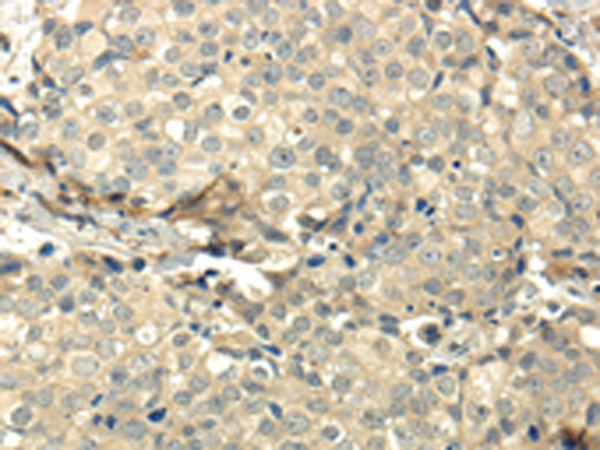

分类: 科研抗体货号: P00244别名:应用: IHC反应种属: Human, Mouse